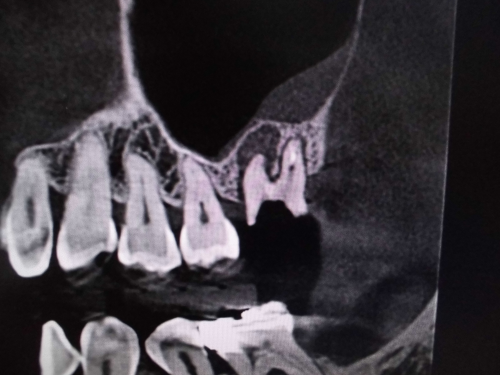

レントゲンでは不明な根尖病巣がCTでははっきり写ります。

同じ患者様です。根管が樋状根になっているのもわかります。